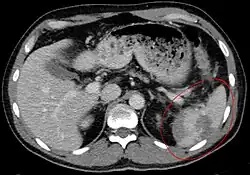

Splenic rupture is usually evaluated by FAST ultrasound of the abdomen.[5] Generally this is not specific to splenic injury; however, it is useful to determine the presence of free floating blood in the peritoneum.[5] A diagnostic peritoneal lavage, while not ideal, may be used to evaluate the presence of internal bleeding a person who is hemodynamically unstable.[6] The FAST exam typically serves to evaluate the need to perform a CT scan.[6] Computed tomography with IV contrast is the preferred imaging study as it can provide high quality images of the full peritoneal cavity.[5]